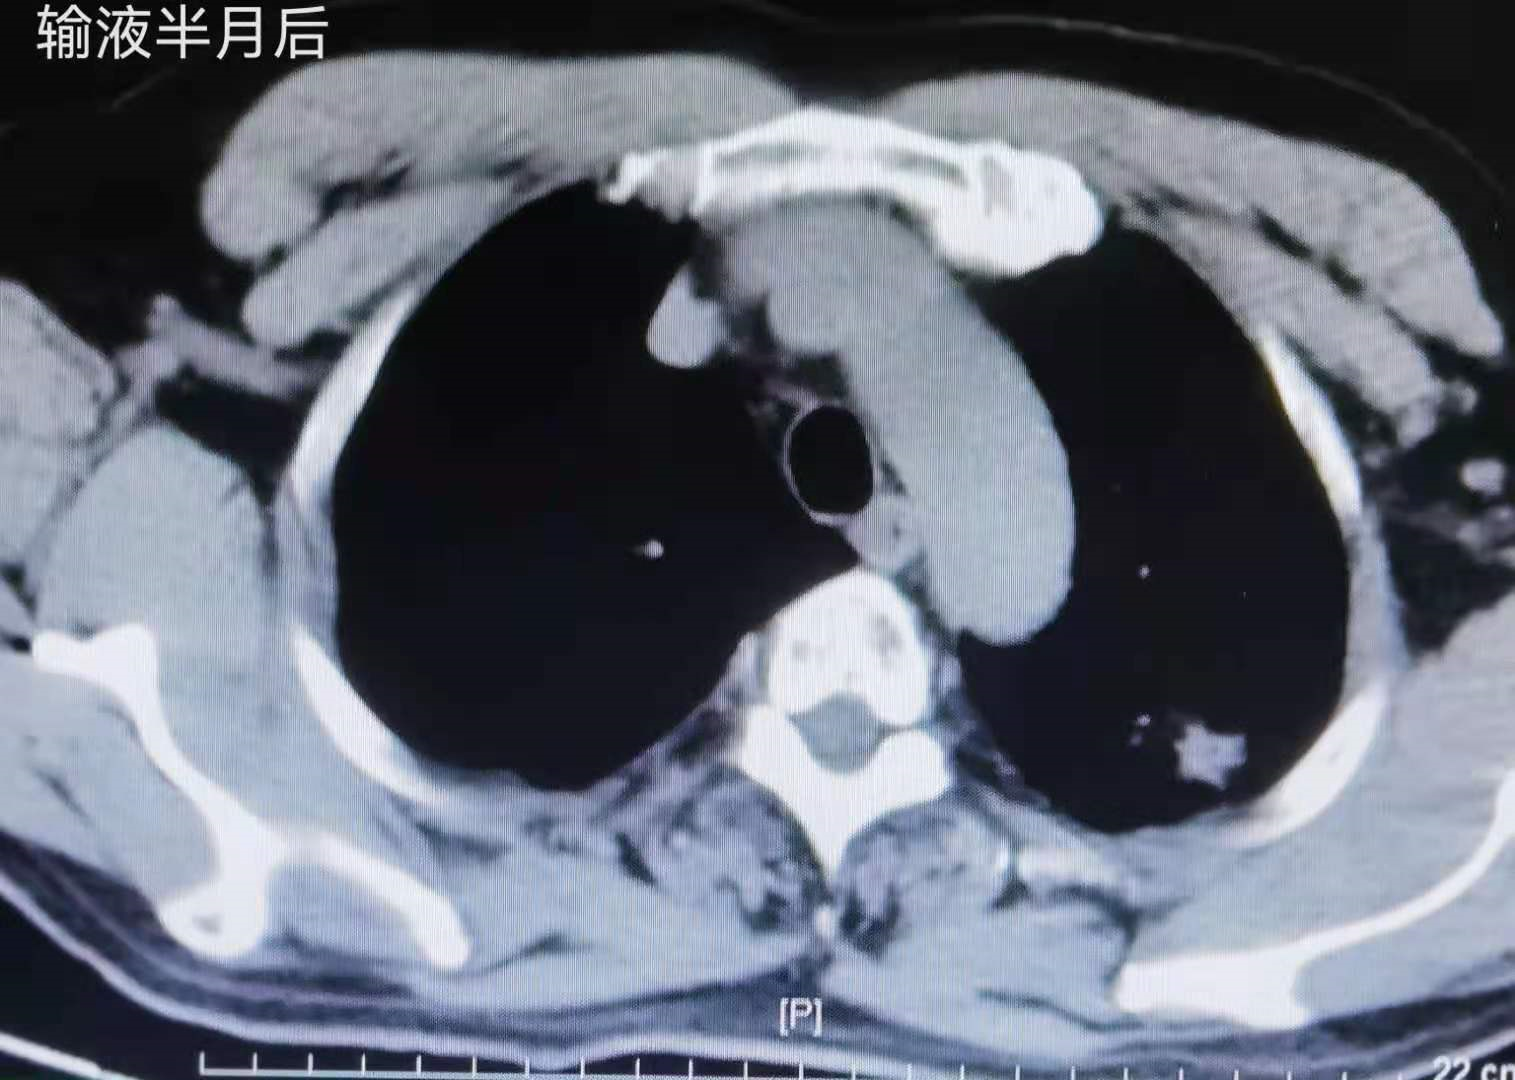

患者 , 居某 , 男 , 68岁 , 患者2016年06月 , 体检查胸部CT:左上肺3.3cm*2cm肿块 , 边缘毛刺 。 经抗炎治疗半月后复查病灶无明显变化 , 纵隔窗病灶恶性征象更明显 。 见图1 , 2 , 3

患者病理分期IB期 , 术后未行任何辅助治疗 , 每年定期复查未见复发转移征象 , 见图4 。 目前手术后已五年 , 达临床治愈 。